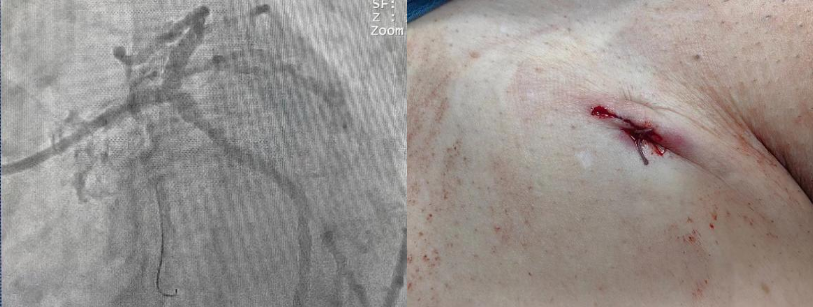

3月7日,西咸院区心内科冠心病介入团队朱舜明副主任医师带领唐治国主治医师、李强强主治医师、张翔住院医师、柳莎莎护士长、崔文宇护师,以及介入导管室团队雷博副护士长、瞿浩主管技师、李炳宇技士,顺利完成物品准备、上机准备、血管评估、穿刺置管等工作,心内科刘博主治医师、梁倩住院医师、刘志远住院医师完成了配血、备血等保障工作,所有医护齐心奋战,整个流程一气呵成,ECMO转机成功。暗红色血液经过膜肺氧合变成鲜红血液,源源不断重返患者体内。术中冠脉造影可见患者左主干末端90%严重狭窄,细小右冠99%狭窄。在ECMO辅助下,心内科介入团队开始进行手术操作。当导丝通过接近闭塞的血管时,患者即出现血流减慢,血压瞬间降至50/30mmHg,透视下心脏几乎不跳动。所有手术人员都捏了一把汗。朱舜明副主任医师迅速指挥抢救,通过提升ECMO转速和流量,并快速用球囊扩张狭窄血管后,患者血流动力学恢复稳定,血压升至110/70mmHg。后续在血管内超声(IVUS)指导下,历时1小时余,完美完成了左主干血运重建。观察患者生命体征平稳后,撤除ECMO并缝合动静脉伤口,体表仅留下不到2cm的痕迹,患者术后胸痛症状明显好转,安返病房,监测生命体征平稳。

介入治疗前造影

介入治疗后造影图及术后ECMO伤口